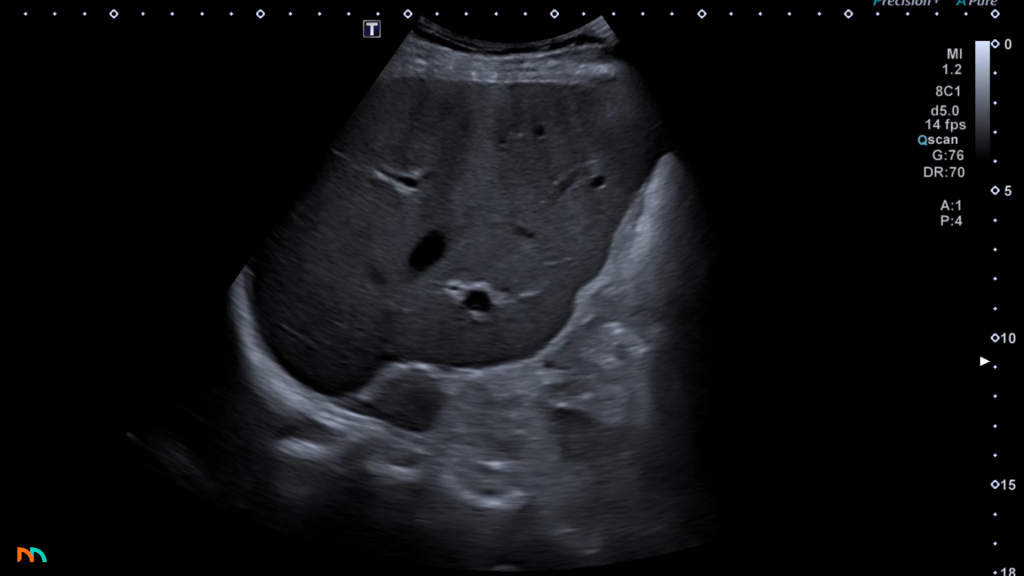

Po prawej stronie pole nadnerczowe jest łatwiejsze do zlokalizowania i zobrazowania. Zazwyczaj mamy bardzo dobre okno akustyczne w postaci prawego płata wątroby. Do tego mamy dodatkowy punkt nawigacyjny w postaci żyły głównej dolnej. Warto zatem zapamiętać, że prawe pole nadnerczowe położone jest pomiędzy górnym biegunem nerki prawej, a żyłą główną dolną, poniżej i do tyłu względem prawego płata wątroby. W tej okolicy w prawidłowych warunkach stwierdzamy jednorodny, echogeniczny obszar tkanek zaotrzewnowych i to właśnie tam znajduje się nadnercze. W przypadku gdy nie widzimy w tym obszarze żadnych separujących się ognisk, uznajemy że obraz pola nadnerczowego jest prawidłowy.